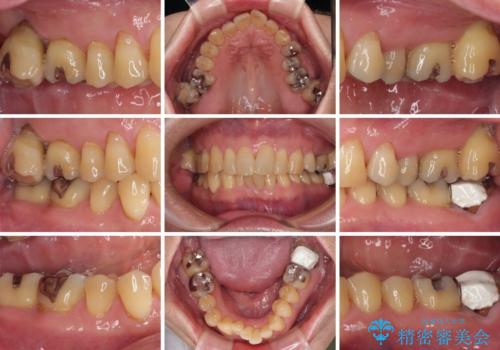

外側に飛び出している歯 部分矯正を用いた奥歯の補綴治療

上顎の奥歯は、左右ともに外側に転位しており、特に右上はむし歯の範囲が広く、根管治療も必要な状態でした。

左下の奥歯は状態が非常に悪く、保存は困難と判断されたため、インプラントによる補綴治療が必要でした。

上顎左右の歯をアンカースクリューを用いた部分矯正により位置を修正し、オールセラミッククラウンにて補綴治療を行うこととしました。

矯正治療に時間はかかりましたが、外側に飛び出した歯が内側に収まったことで、非常に歯が磨きやすくなったとのことでした。